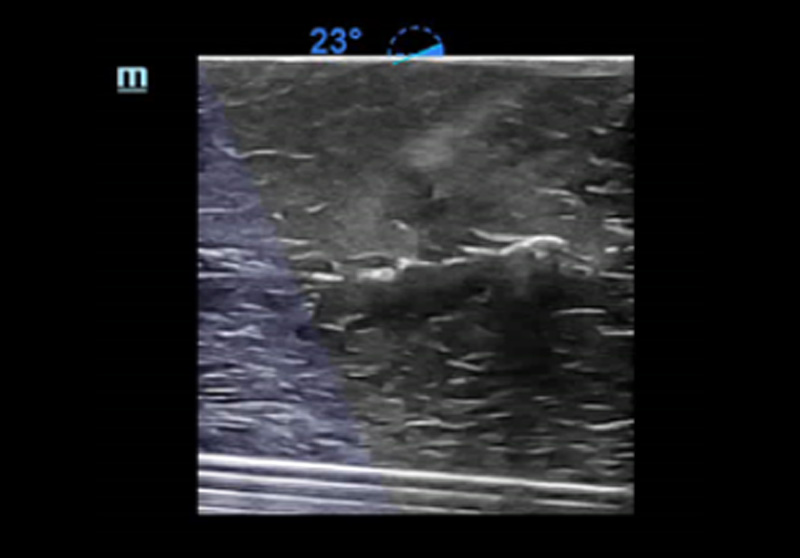

3Smart IVC

Automatic measurement of IVC (Inferior Vena Cava) parameters, helps for volume status assessment and guides the fluid therapy. A graph of parameters change about CI or DI and IVCV for monitoring the change of critical ill patients.